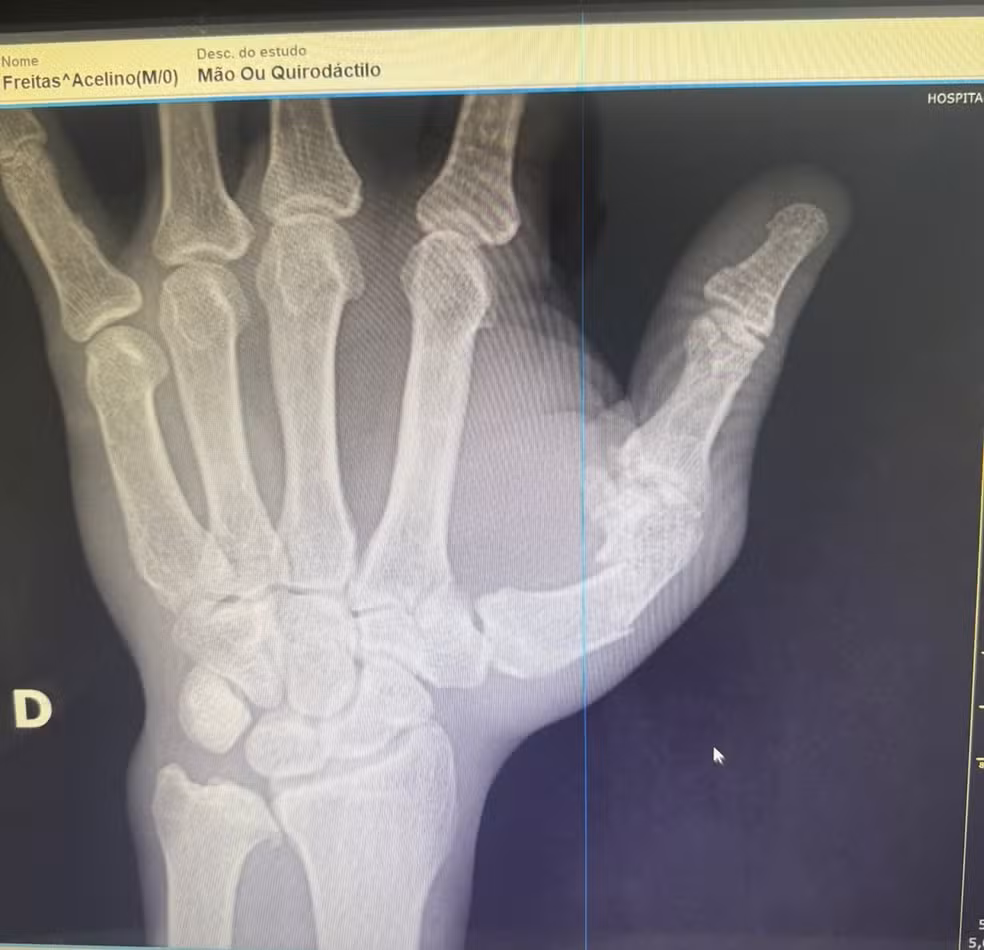

Popó passa por cirurgia na mão após briga generalizada — Foto: Divulgação

Imagens de raio-X, às quais o g1 teve acesso, mostram uma fratura na mão direita do atleta. A equipe de Popó não detalhou a lesão, mas confirmou que ele “quebrou a mão na confusão”. A fratura é uma consequência da briga generalizada que marcou o fim da luta contra Wanderlei Silva, no último sábado (27), em São Paulo.

Ortopedista pela Universidade de São Paulo e especialista em lesões esportivas da Clínica Sartor, Bruno Butturi afirma que a radiografia indica uma fratura diafisária do primeiro metacarpo, principal osso do polegar.

Trata-se de um osso fundamental para a mobilidade da mão porque sustenta o movimento de pinça, que permite a preensão firme de objetos e é considerado um dos diferenciais anatômicos do ser humano em relação a outros primatas.

“É uma lesão da base do polegar. O osso está quebrado e desviado, o que exige cirurgia. Se fosse apenas imobilizado, o risco de sequelas funcionais seria alto, especialmente em um atleta que depende das mãos para competir”, explica Butturi.

Segundo o médico, o tratamento é cirúrgico e envolve a fixação do osso com placa e parafusos ou, em alguns casos, com pinos introduzidos por pequenas incisões.